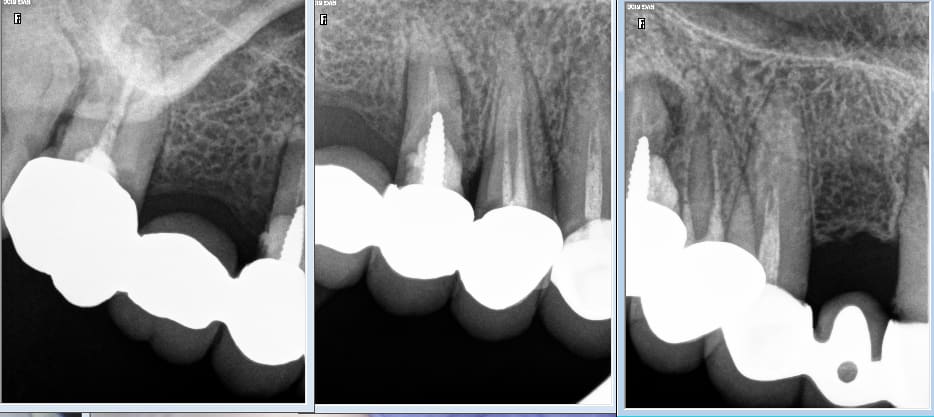

IC ceram 23 + stellite.

Plus longtemps que les dents restantes de l'autre coté. La patiente ne voulait pas passer au complet. Elle est au courant. Et passage au complet meme topo. One shot je me servirais de cette 23 comme base de réaccrochage de la camera. Ca s'appelle de l'efficience au sein d'un système de santé collectiviste. -)))

Pas mal. Attachements + augmentation de DV en plus.

Ben écoutes on fait ce qu'on peut pour réduire le temps consacré à la prothèse pour rattraper le déficit généré par les endos et les soins payés à coup de trique par la sécu. Tu préfèrerais que je gagne du temps sur l'endo ? Je recommence : one shot. -)))

Ca te pousse à t'améliorer en fixe : t'évites de toucher la gencive pendant tes tailles : moins ca saigne mieux c'est.

La modernité ce serait le no post no crown... Nous en France on vient de créer le full post full crown... :)))